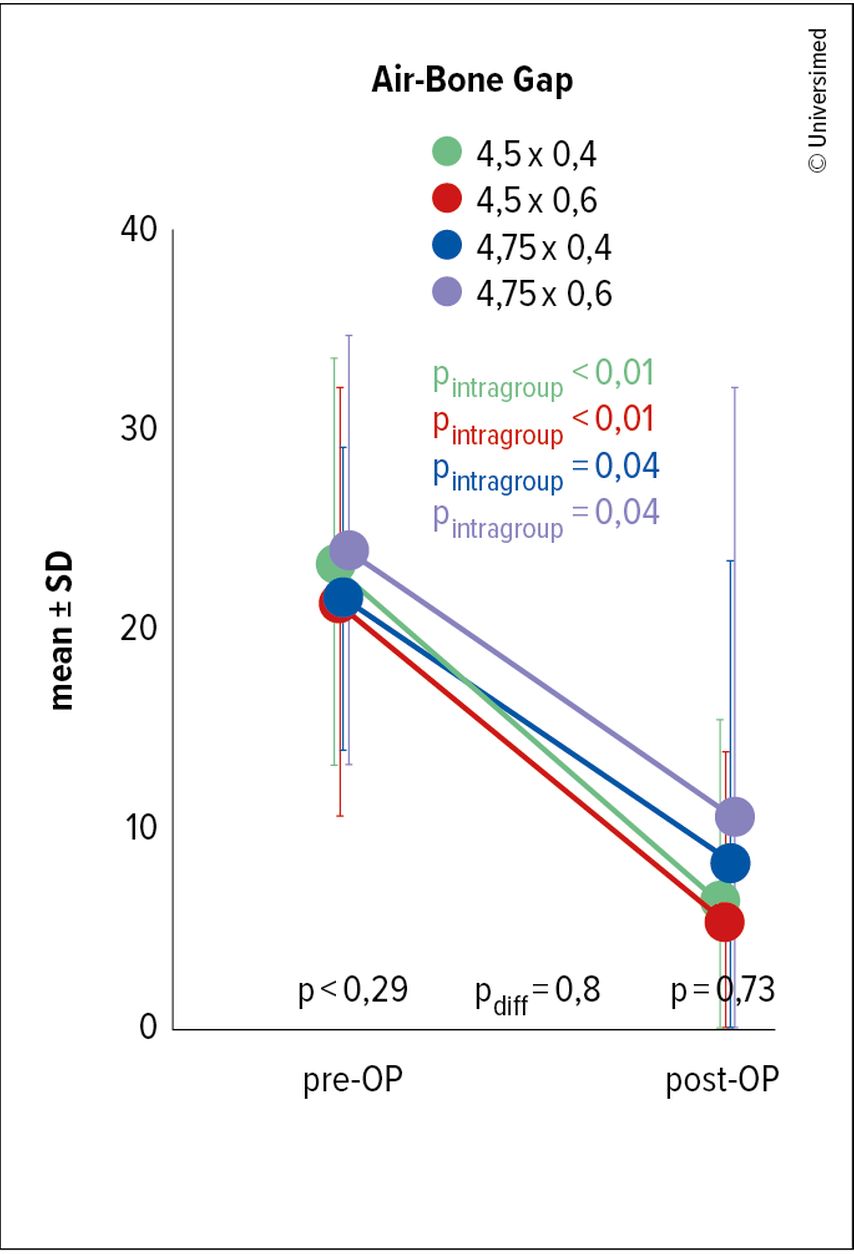

Außerdem war die Verringerung der Schallleitung mit einer Reduktion von im Schnitt 22,6dB auf 6,8dB signifikant (Abb. 6).